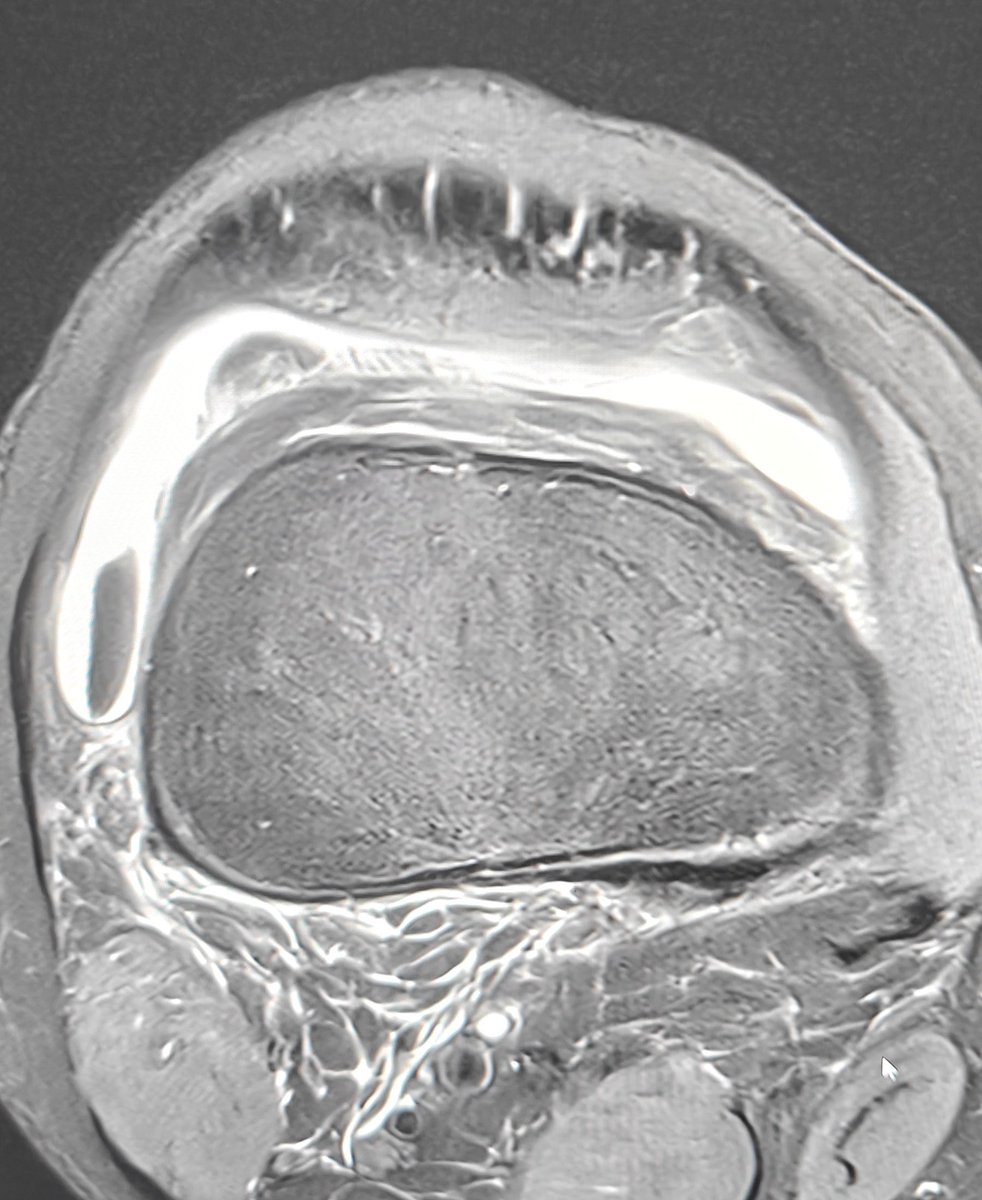

•Adolescent - acute chondral fracture trochlear. •Sharp edges give it away. •Maybe have been chondral delamination before 🤔 •Displaced fragment within the lateral gutter. #mskrad #foamrad

Neeraj Purohit tweet mediaNeeraj Purohit tweet mediaNeeraj Purohit tweet media